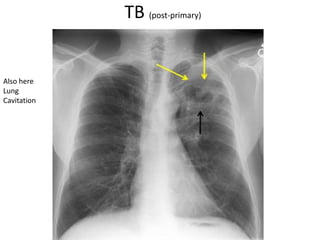

Also here

Lung

Cavitation

Infection in

both lungs is

marked by

white arrow-

heads, and the

formation of a

cavity is

black arrows.